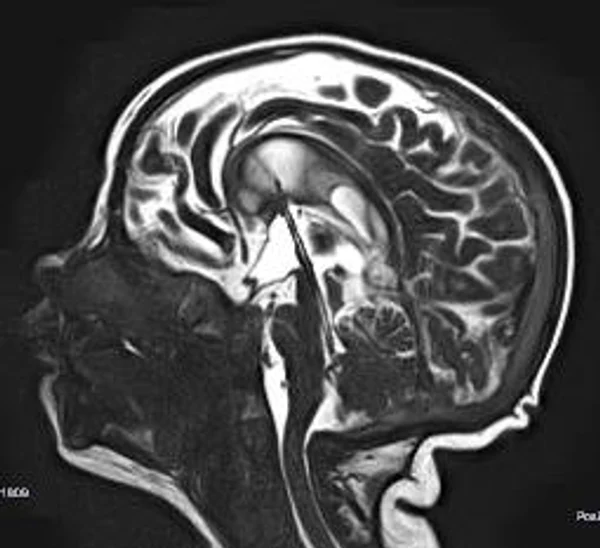

Гидроцефалия

Основной причиной гидроцефалии является окклюзия ликворных путей, встречающаяся у новорожденных детей в 60-70% случаев, к 3 годам частота окклюзионной гидроцефалии достигает 90%. Поэтому основной задачей лечения гидроцефалии являются устранение окклюзии ликворных путей, восстановление циркуляции ликвора и нормализация внутричерепного давления. В настоящее время эти задачи успешно позволяют решить эндоскопические методы хирургического лечения гидроцефалии. Эндоскопические операции проводятся нами во всех возрастных группах, включая недоношенных новорожденных детей, при разных локализациях и количествах окклюзий. При этом если эндоскопическая перфорация дна III желудочка (син.: эндоскопическая III-вентрикулостомия) малоэффективна у детей до 2-3-х летнего возраста, то новые методы эндоскопических операций, направленные на реканализацию естественных путей оттока ликвора с имплантацией стента (например эндоскопическая акведуктопластика, стентирование водопровода мозга) позволяют избежать имплантации шунтирующих систем у большинства пациентов с окклюзионными формами гидроцефалии. С целью снижение объема секреции ликвора и увеличения эффективности эндоскопических опеарций в некоторых случаях в комплексе с другими эндоскопическими операциями проводится эндоскопическая плексусэктомия. Операция заключается в коагуляции сосудистых сплетений боковых желудочков с последующим удалением их гломусных частей. Эндоскопические операции также проводятся при дисфункции ранее установленных шунтирующих систем у пациентов с окклюзионной гидроцефалией, что часто избавляет пациента от «шунт зависимости» и создает условия для удаления шунта. Имплантация ветрикулоперитонеальных, вентрикулоатриальных и др. шунтирующих систем нами применяется при сообщающейся форме гидроцефалии. У пациентов с окклюзионными формами гидроцефалии шунтирующие операции проводятся только при неэффективности ранее проведенных эндоскопических операций.